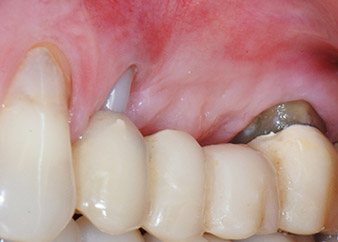

Междинен резултат след два месеца

Фигури 17 и 18 показват клиничния резултат два месеца след операцията. Зъб 24 показва намалена подвижност на Милър клас 1 и меките тъкани не са възпалени. Сондирането е избегнато на този етап, за да се избегне повторно възпаление и нарушение на епителната надстройка. Планиран е контролен преглед за повторно отваряне и поставяне на оздравителни абатмънти, шест месеца след поставяне на имплантите.

Два месеца след операцията, пациентката не чувства болка.

Фиг. 17: Два месеца след операцията, пациентката не чувства болка и зоната не е възпалена.

след операцията

Фиг. 18: Зъб 24 вече показва по-малко подвижност.

Прогноза и опции за възстановяване

На прегледа след два месеца, мобилността на останалия "дентален елемент" 24 вече е намалена от Милър 2 на Милър 1. Захващането на меките тъкани е на нивото на съседния зъб 23. Освен това, няма ендодонтски или периодонтални симптоми, така, че прогнозата трябва да се коригира.

Въпреки това, тъй като голяма част от букалната и проксималната кост липсва и композитното изграждане се простира до апикалната част корена, не се очаква по-високо ниво на захващане в следствие на биологични причини (Sculean et al., 2008).